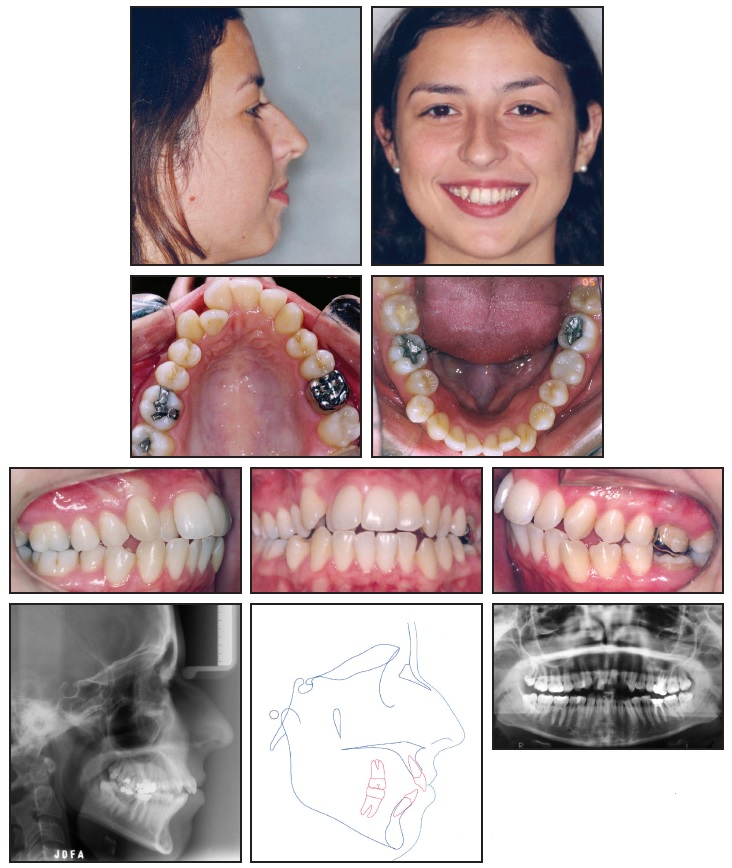

Tooth Extraction Procedure Aftercare Recovery best sale, Surgical extraction of mandibular third molar a rational and safe best sale, Dental extraction Wikipedia best sale, From Start To Finish How Long Does A Tooth Extraction Take best sale, Dry Socket What It Is Symptoms Treatment best sale, Upper right 1st molar extraction with interradicular septum. A best sale, Dental extraction Wikipedia best sale, Tooth Extraction Home Care Instructions Cobblestone Dental Care best sale, Los Angeles Wisdom Tooth Extraction Questions Dr. Jamie Sands best sale, Tooth extraction Information Mount Sinai New York best sale, Physics Forceps Upper Molar Tooth Extraction Cytoplast Barrier Grafting best sale, Tooth Extractions Milton FL Thrive Dental Associates best sale, Why Replace A Back Molar Marietta Tooth Replacement Muskingum best sale, Your Guide To Surgical Tooth Extraction Grand Central Dentistry best sale, Complications of Dental Extractions Geeky Medics best sale, The Beginner s Guide to Tooth Extraction Family Choice Dental best sale, Tooth Extractions Drexel Hill PA Bloomfield Dental best sale, Comparing Tooth Extraction vs Root Canal What s the Difference best sale, Tooth Extraction best sale, Tooth Extraction Boston MA Dentist James M. Stein DMD best sale, Tooth Extraction Removal Bupa Dental Care UK best sale, Tooth Extraction Cost for 2021 Procedure Risks Recovery best sale, Wisdom Tooth Extraction Removal Procedure Pain Cost Recovery best sale, Healing of local gingival tissue following tooth extraction best sale, What Happens When You Have To Extract and Replace a Molar Spear best sale, Asymmetrical Extraction in an Adult Class II best sale, Tooth Extraction Dr. Christian Chung D.D.S best sale, Tooth Extractions Moorehead Dentistry Batavia OH best sale, Oral Surgery in NYC Tooth Extraction 209 NYC Dental best sale, Dental extraction Wikipedia best sale, Tooth Extractions best sale, Badly Infected Tooth Extraction Procedure With Pus Coming Out of The Tooth best sale, Fast Tooth Extractions at a Great Price Lake Lanier Smiles best sale, Treatment Options After Tooth Extraction best sale, What you need to know before a tooth extraction Top Doctors best sale.

Tooth Extraction Procedure Aftercare Recovery best sale, Surgical extraction of mandibular third molar a rational and safe best sale, Dental extraction Wikipedia best sale, From Start To Finish How Long Does A Tooth Extraction Take best sale, Dry Socket What It Is Symptoms Treatment best sale, Upper right 1st molar extraction with interradicular septum. A best sale, Dental extraction Wikipedia best sale, Tooth Extraction Home Care Instructions Cobblestone Dental Care best sale, Los Angeles Wisdom Tooth Extraction Questions Dr. Jamie Sands best sale, Tooth extraction Information Mount Sinai New York best sale, Physics Forceps Upper Molar Tooth Extraction Cytoplast Barrier Grafting best sale, Tooth Extractions Milton FL Thrive Dental Associates best sale, Why Replace A Back Molar Marietta Tooth Replacement Muskingum best sale, Your Guide To Surgical Tooth Extraction Grand Central Dentistry best sale, Complications of Dental Extractions Geeky Medics best sale, The Beginner s Guide to Tooth Extraction Family Choice Dental best sale, Tooth Extractions Drexel Hill PA Bloomfield Dental best sale, Comparing Tooth Extraction vs Root Canal What s the Difference best sale, Tooth Extraction best sale, Tooth Extraction Boston MA Dentist James M. Stein DMD best sale, Tooth Extraction Removal Bupa Dental Care UK best sale, Tooth Extraction Cost for 2021 Procedure Risks Recovery best sale, Wisdom Tooth Extraction Removal Procedure Pain Cost Recovery best sale, Healing of local gingival tissue following tooth extraction best sale, What Happens When You Have To Extract and Replace a Molar Spear best sale, Asymmetrical Extraction in an Adult Class II best sale, Tooth Extraction Dr. Christian Chung D.D.S best sale, Tooth Extractions Moorehead Dentistry Batavia OH best sale, Oral Surgery in NYC Tooth Extraction 209 NYC Dental best sale, Dental extraction Wikipedia best sale, Tooth Extractions best sale, Badly Infected Tooth Extraction Procedure With Pus Coming Out of The Tooth best sale, Fast Tooth Extractions at a Great Price Lake Lanier Smiles best sale, Treatment Options After Tooth Extraction best sale, What you need to know before a tooth extraction Top Doctors best sale.